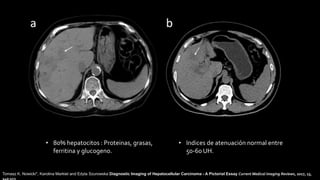

• 80% hepatocitos : Proteinas, grasas,

ferritina y glucogeno.

• Indices de atenuación normal entre

50-60 UH.